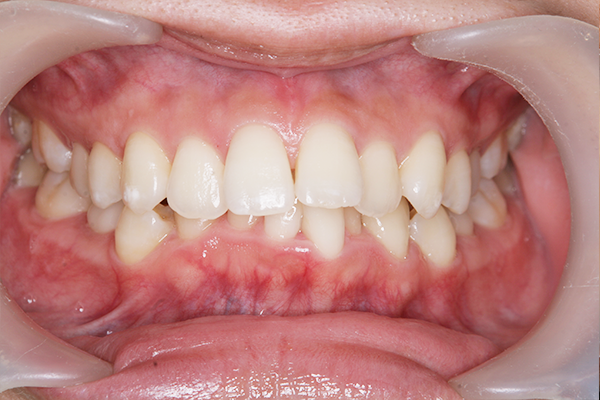

術前

術後

オフィスホワイトニング 38,500円

主訴 歯の色が気になると来院。

全体クリーニング後、1回の施術で効果を実感でき、3回目で希望の白さに近づけた。

治療期間:1日(写真は1回目の処置後)

副作用・リスク:一時的に知覚過敏の症状が出る可能性あり